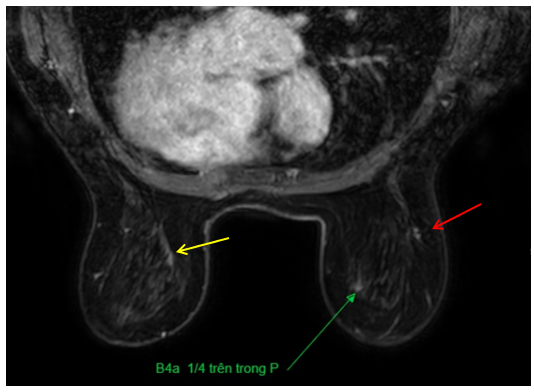

Cộng hưởng từ tuyến vú 2 bên:

Vú phải: Vị trú khoảng 9h vùng đuôi vú, có nốt kích thước 8×11 mm (BIRADS 4B), kèm dải ngấm thuốc chạy về phía trước dài 27mm. Vị trí 2h cách núm vú 3cm có nốt nhỏ đướng kính 5mm (BIRADS 4A).

Vú trái: Hình ảnh tổn thương kích thước 29x77mm lan rộng ½ dưới vú trái (BIRADS 4C), thâm nhiễm núm vú, gây dày da vùng quanh núm vú.

Hình 2:Cộng hưởng từ tuyến vú (Mũi tên vàng: Tổn thương BIRADS 4C; Mũi tên đỏ: Tổn thương BIRADS 4B; Mũi tên xanh: Tổn thương BIRADS 4A)